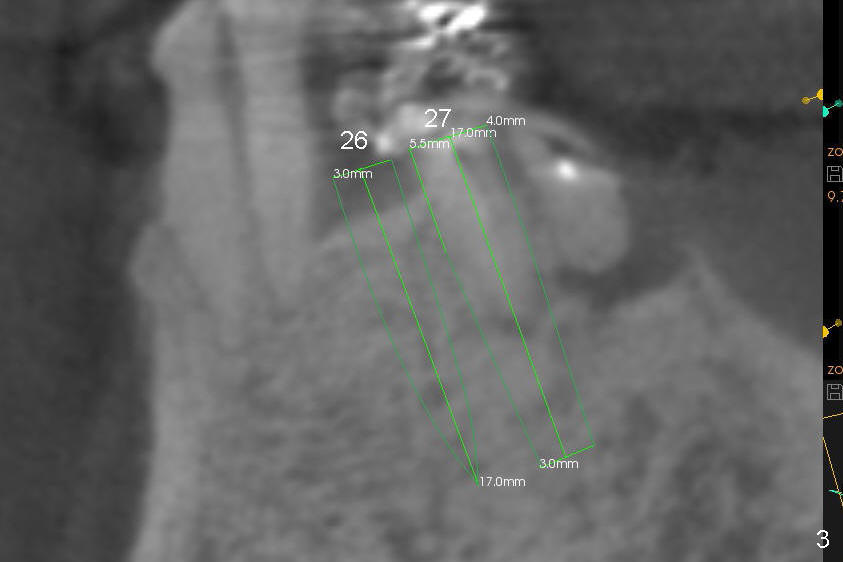

Fig.1-3 are CBCT sagittal sections of the lower right quadrant, whereas Fig.4-8 are coronal sections. The lower left quadrant has been restored.